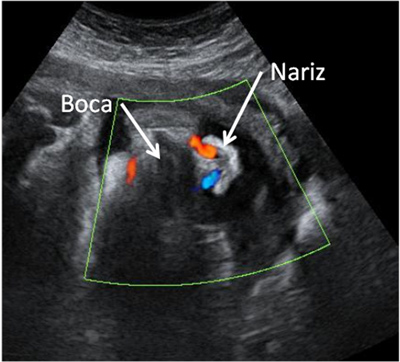

Ecografía Doppler color donde se puede apreciar como el feto "respira" líquido amniótico. Las líneas de color rojo y azul a la salida de los orificios nasales ponen de manifiesto las columnas de líquido que el feto expulsa por su nariz (el Doppler color es capaz de evidenciar líquidos en movimiento, en este caso líquido amniótico expulsado a través de la nariz).